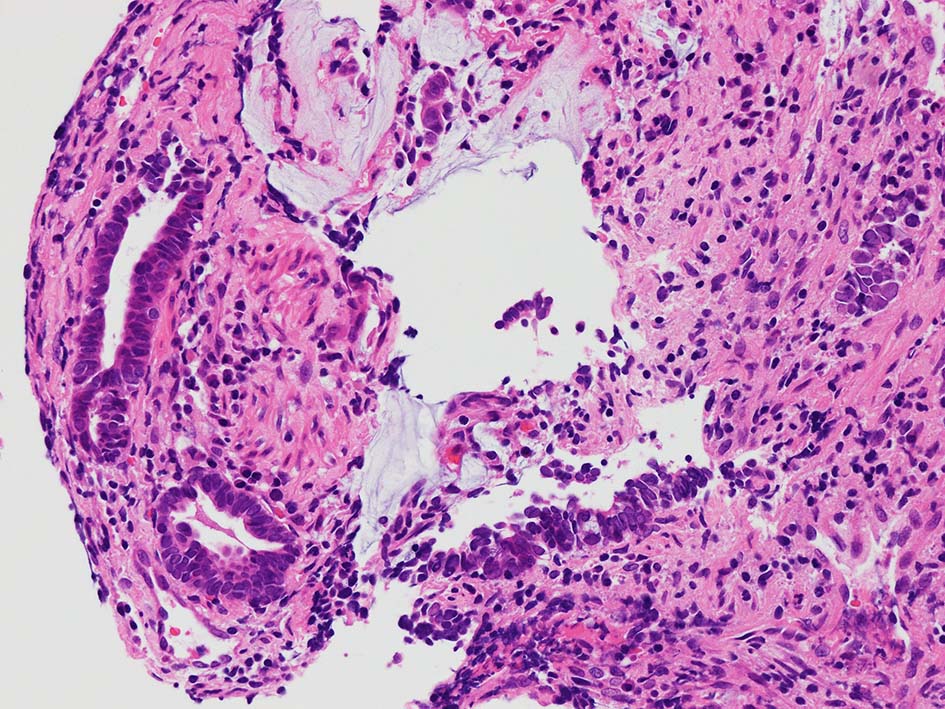

desmoplastic fibrosis, 粘液浸潤のみられる組織片にはsig, porのadenocarcinoma浸潤が確認される.

neutrophilic exudate の付着する腸管型腺癌部分. 核はより腫大し円形、vesicularとなっている. 上記腸管型とはCK20, CK7のそまりが異なっていた. 変性のためかもしれない.